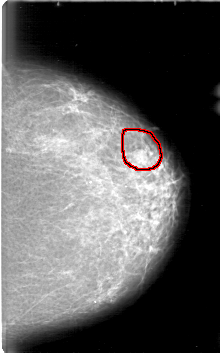

D_4089_1.LEFT_CC

LEFT_CC LINES 5281 PIXELS_PER_LINE 3286 BITS_PER_PIXEL 12 RESOLUTION 43.5 OVERLAY

FILE: D_4089_1.LEFT_CC.OVERLAY

TOTAL_ABNORMALITIES 1

ABNORMALITY 1

LESION_TYPE MASS SHAPE OVAL MARGINS OBSCURED

ASSESSMENT 0

SUBTLETY 3

PATHOLOGY BENIGN

TOTAL_OUTLINES 1

BOUNDARY